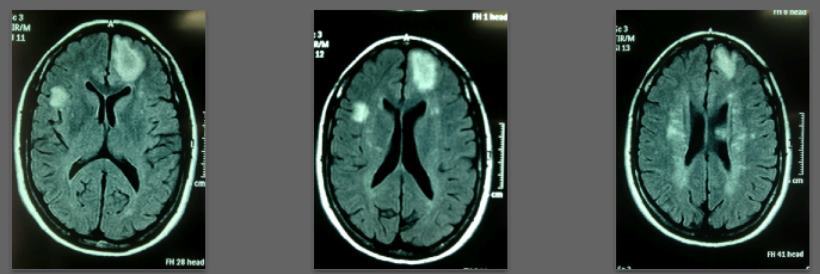

Specifically: Recent lesions appeared partially repaired or disappeared on MRI scans after one and two years of treatment.

Before/after MRI images for one of 1,000+ patients of Dr. Coimbra

PDF is attached at the bottom of this page

2008 Convulsive seizures Diagnosis: Balo’s concentric hemiparesis

Starting daily dose 25,000 IU; increased in stages to 80,000 IU on October 28, 2010. Asymptomatic since 2010.

2008 MRI

2013 MRI